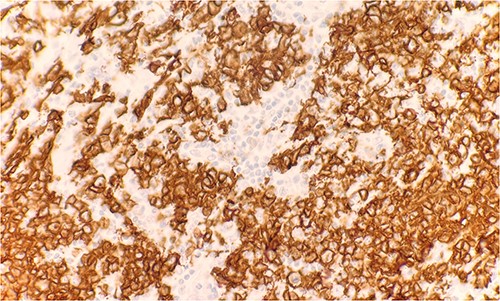

Microscopic examination reveals skin and subcutaneous tissue with atypical nodular nested lymphoid infiltrate in the dermis. The infiltrate is composed of intermediated cells with irregular nuclei, dispersed chromatin and variably conspicuous nucleoli mixed with large cells (Fig. 1). The atypical cells are positive for CD20 (Fig. 2) and BCL6 (Fig. 3). The morphological findings along with the skin location are consistent with primary cutaneous follicle center lymphoma (PCFCL).

Immunohistochemical stain reveals atypical lymphoid cells are positive for CD20. IHC 40×.